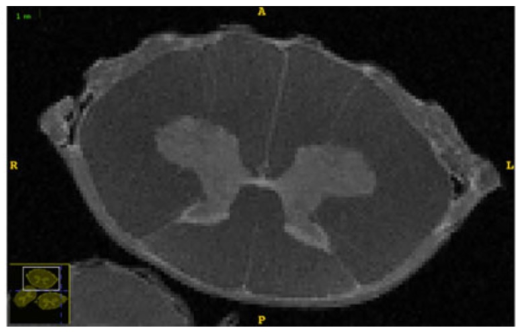

Now we consider the simulation of a real-world application: cross-sections of the spinal cord. Anatomically, the spinal cord consists of gray and white matter, with the gray matter forming an H-shaped (or butterfly-shaped) structure in cross-section, surrounded by the white matter. As shown in Fig. 1(a), the inner marked in gray represents the gray matter, surrounded by the white matter (in the darker area). There is the pia mater adheres to the white matter. It is known (e.g., see [16, 28]) that the spinal cord can be modeled as a poroelastic medium, with the flow and deformation in the spinal cord being governed by the linear poroelasticity equations. These modeling and studies are of importance to the understanding and treatments of spinal cord injuries; e.g., see [33].

Following [16, 28] we consider a scenario with the parameter values listed in Table 3. Notice that Young’s modulus and the permeability have different values in the gray and white matter and pia mater. The system has an antero-posterior diameter of 0.9 cm and a transverse diameter of 1.3 cm. Fig. 1(b) shows a mesh used for the problem, which was smoothed using a moving mesh method through the Matlab package MMPDElab [9]. The domain boundary is divided into three segments as

Figure 1: (a) High-resolution DTIs from a sheep cadaveric spinal cord [28]. (b) A sample triangular mesh with 5724 elements for the simulation.